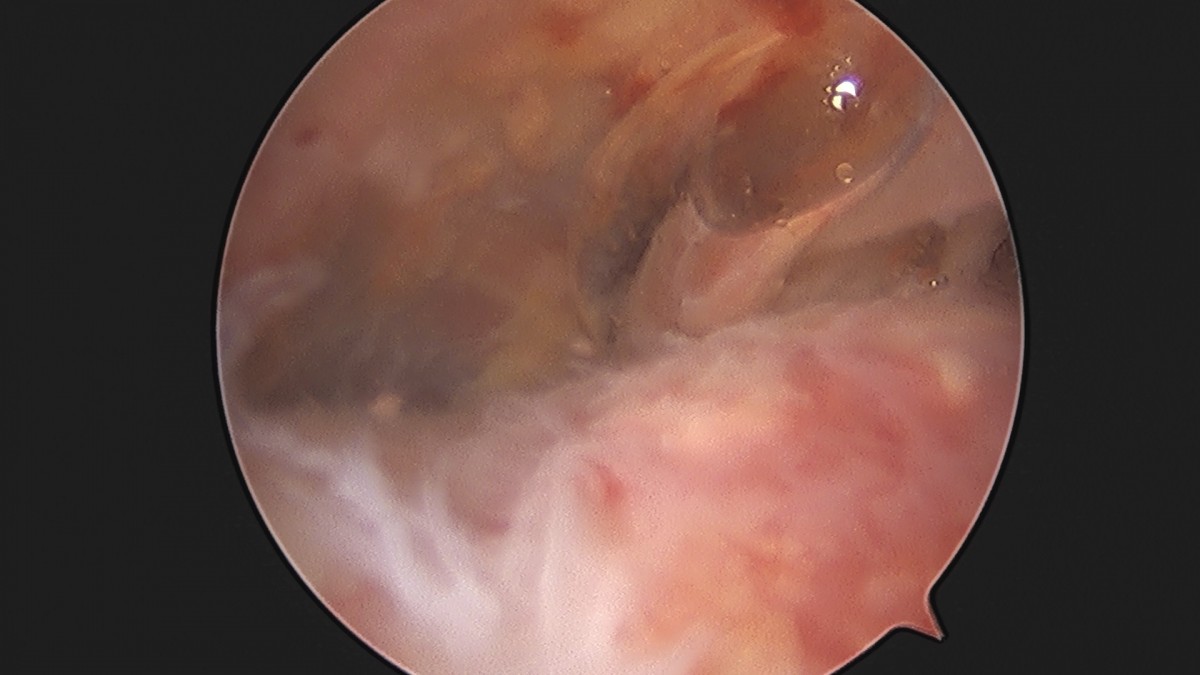

이재상원장님 어깨 석회 제거술 조광O 환자

dae765e4d9ac96aee867c9d6292d8784_1758004693_7301.jpg